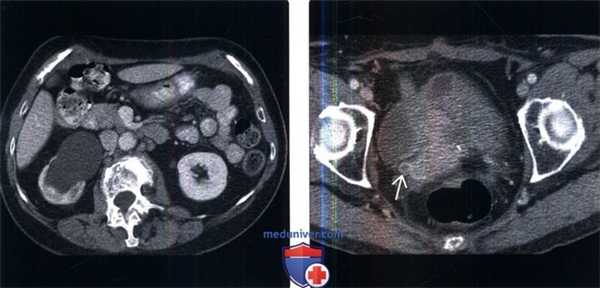

(Слева) КТ почек с контрастированием, аксиальный срез: заметный правосторонний гидронефроз со стойкой нефрограммой.

(Справа) На срезе мочевого пузыря того же пациента определяется заметный гидроуретер. Обратите внимание на сужение просвета и кольцевидное утолщение стенки дистального отдела мочеточника. У пациента в анамнезе внешнее облучение по поводу рецидива меланомы влагалища. Данные визуализации сами по себе неспецифичны. Учитывая анамнез и локализацию, тем не менее, эти признаки указывают на радиационно - индуцированный уретерит.